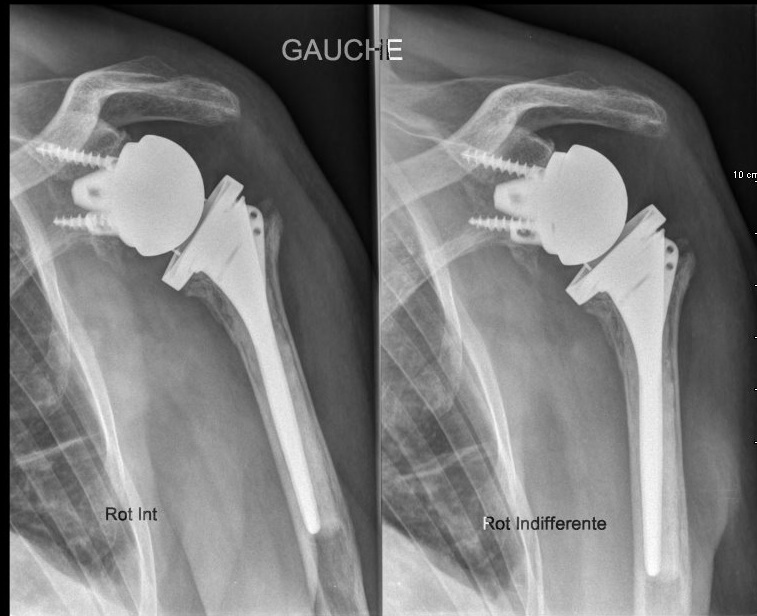

La pose d’une prothèse d’épaule aboutit dans la grande majorité des cas à un bénéfice pour le patient, indolence et amélioration de la fonction.

Parfois malheureusement les suites ne sont pas simples, raideur longue à récupérer, persistance de douleurs mais il existe également des complications qui peuvent aboutir à des réinterventions: